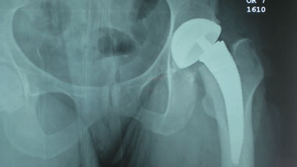

| The next case was also a small female with a slightly larger femoral neck and acetabulum |

| Slightly more neck was removed |

| Ben Hur |

| AWL no difficulty |

Slightly more neck resection |

| Progression of routine use of rasps |

Some fine tuning with a high speed burr was done since we were on cortical bone.

This is not necessary but was helpful in getting a more custom fit |

Good fit of final stem.

Stability was very impressive |